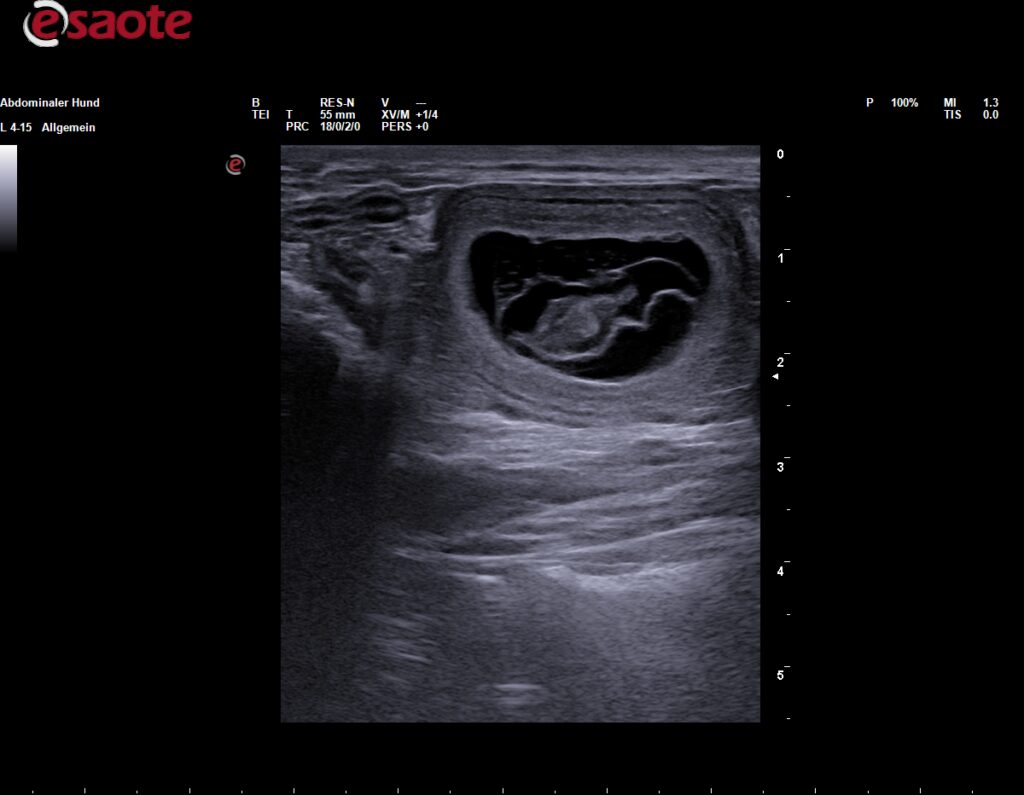

Am 03.09.2025 hat der Ultraschall es bestätigt, Baya ist trächtig! Es wurden mindestens 4 Welpen gesehen, es bleibt spannend. In der ersten Oktoberwoche kommt unser G-Wurf zur Welt.